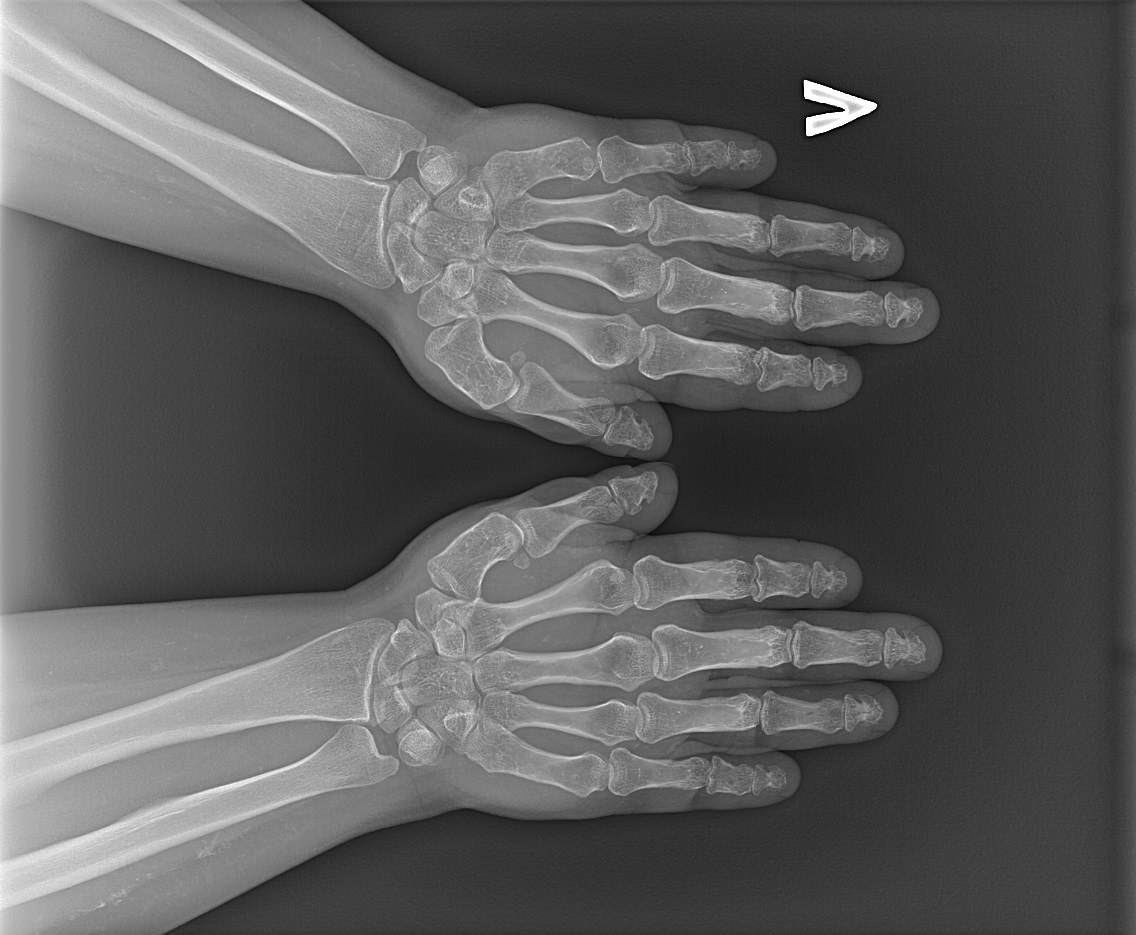

В ФГБУ НМИЦ эндокринологии наблюдается женщина 35 лет с ожирением, низкорослостью, депрессивными расстройствами, нарушениями кальций-фосфорного обмена, гипотиреозом. С 3 лет у пациентки отмечались тонические судороги на фоне фебрильной лихорадки и периодические миалгии. Впервые обследование проведено в 12 лет в связи с появлением карпопедальных спазмов, когда была выявлена гипокальциемия (Са общ. 1,3, при норме 2,0–2,6 ммоль/л), гиперфосфатемия (2,66 ммоль/л при норме 0,7–1,6) на фоне повышенного уровня ПТГ (268 пг/мл). Во время обследования в стационаре также впервые обратили внимание на особенности фенотипа: у девочки отмечалось ожирение, укорочение IV и V пястных и плюсневых костей (рис. 1, 2), пальпировались плотные подкожные образования, не спаянные с окружающей тканью, безболезненные. Гистологическое исследование биоптата образований доказало наличие подкожных кальцификатов с распространением в перимизий. По данным мультиспиральной компьютерной томографии (МСКТ) головы выявлено обызвествление базальных ядер и субкортикальных отделов головного мозга (рис. 3). Был установлен диагноз «псевдогипопаратиреоз Iа типа». Молекулярно-генетическое исследование подтвердило наличие мутации в гене GNAS – гетерозиготная мутация GNAS в сайте сплайсинга с.585+2Т>С. По поводу резистентности к ПТГ назначен альфакальцидол, в последующем к терапии были добавлены препараты кальция. Прием препаратов осуществлялся под контролем показателей кальция крови с периодической коррекцией дозы. В 20 лет впервые выявлен субклинический гипотиреоз и назначена заместительная терапия препаратом левотироксина натрия с дальнейшей коррекцией дозы в зависимости от уровня ТТГ при контроле в динамике. Клинических признаков гипогонадизма не отмечалось: менархе в 12 лет, менструальный цикл регулярный. При сборе семейного анамнеза не было выявлено особенностей, указывающих на возможность наличия у родственников НОО или гипокальциемии: родители нормального роста, брахидактилии, подкожных образований у них не имеется, судорожных эпизодов или криптогенной эпилепсии ни у родителей, ни у ближайших родственников не отмечалось. У пациентки нет детей, но было 4 беременности, все окончившиеся абортами. Одна беременность – замершая, один аборт по желанию пациентки, 2 последние беременности были прерваны после получения результатов пренатальной диагностики, доказавшей наличие у плода той же мутации в гене GNAS, что и у матери.

Рис. 1. Брахидактилия: выраженное укорочение V пястной кости слева.

В 35 лет пациентка поступила в НМИЦ эндокринологии с жалобами на судорожный синдром. При осмотре обращали на себя внимание низкорослость (рост 148 см), ожирение (87 кг, ИМТ 39) с лунообразным лицом, брахидактилия (рис. 4, 5), подкожные кальцинаты, положительный симптом Хвостека. При сжатии кистей в кулак отмечалась сглаженность в области IV–V пястно-фаланговых суставов – брахиметафалангизм (рис. 6). В ходе обследования была выявлена декомпенсация по кальций-фосфорному обмену и гипотиреозу: гипокальциемия (Са ион. 0,87 ммоль/л при норме 1,03–1,29), гиперфосфатемия (1,81 ммоль/л при норме 0,74–1,52), повышение уровня ПТГ до 136 пг/мл (15–65), гипотиреоз (ТТГ 7,37 мМЕ/л при норме 0,64–5,76, св.Т4 8,72 пмоль/л при норме 11,5–20,4) при нормальном уровне аутоантител (АТ) (АТ к тиреопероксидазе (ТПО) 1,77 МЕ/мл, при норме 0–5,6) и отсутствии эхо-признаков аутоиммунного тиреоидита по данным УЗИ щитовидной железы (рис. 7). В суточном анализе мочи гипокальциурия 0,804 ммоль/сут (2,5–8), 0,37 мг/кг/сут, гипофосфатурия – 12,52 ммоль/сут (13–42). Беседа с пациенткой выявила ряд психологических проблем, появление которых сама женщина связывала с тяжелым переживанием последнего аборта: на фоне депрессии перестала следить за питанием и регулярным приемом препаратов, отмечались прогрессирующий набор веса и периодическая боль в мышцах, развившаяся в итоге в карпопедальный спазм. Проявления острой гипокальциемии были купированы введением раствора кальция глюконата; показатели кальций-фосфорного обмена и функционального статуса щитовидной железы нормализовались после восстановления и коррекции приема альфакальцидола и левотироксина натрия. По поводу имеющейся депрессии получает антидепрессанты под наблюдением психоневролога.